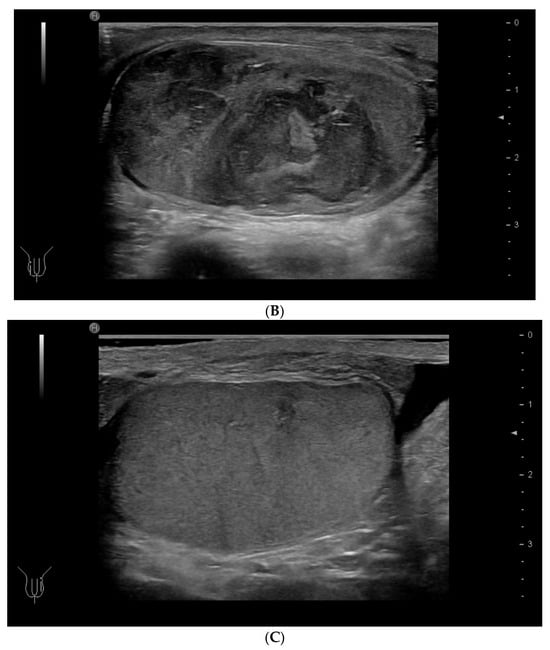

4.3. Elastography in Testicular Lesions